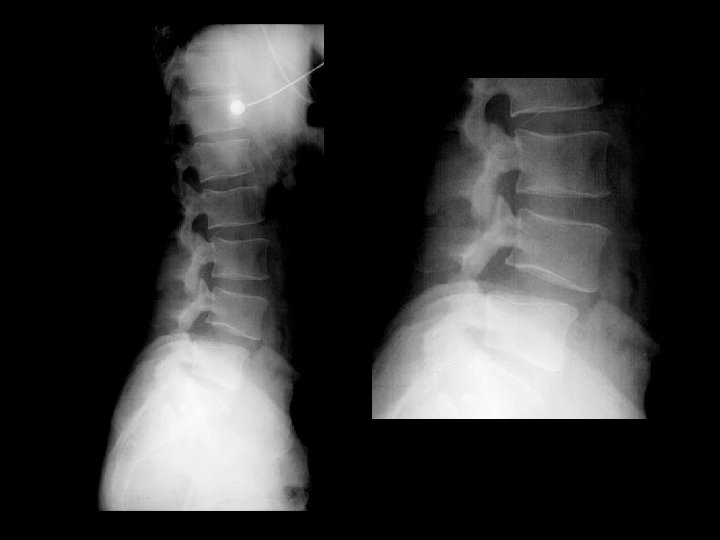

Ankylosing Spondylitis • Findings: – fused SI joints – right hip erosions – lumbar syndesmophytes • Sero-negative chronic inflammatory disease • Starts in the low back and progesses upward • ddx (sacroilitis) – bilateral • ank spond • IBD – unilateral • Reiter’s • psoriasis